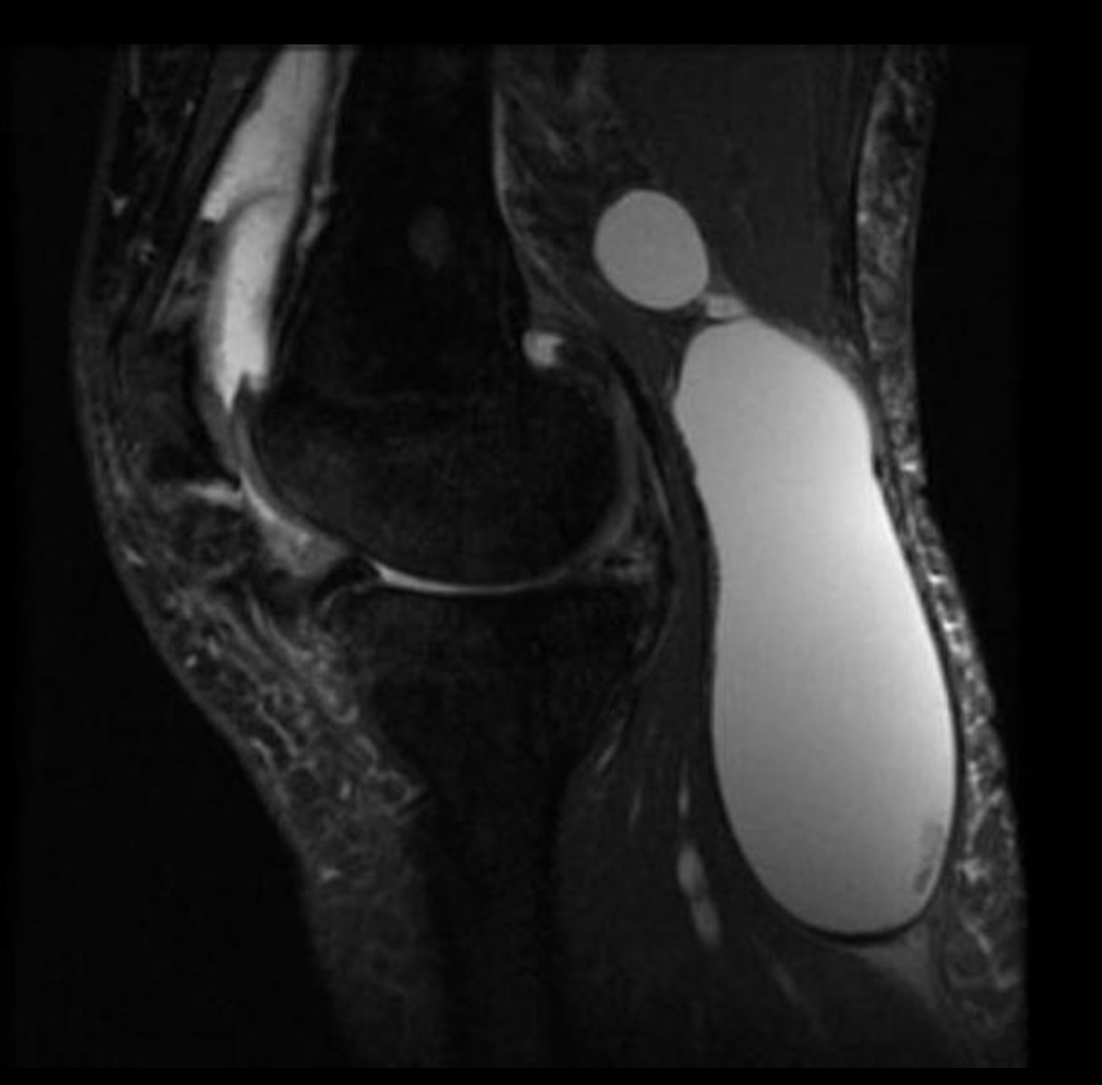

Rezonans magnetyczny cysty Bakera (MRI)

Rezonans magnetyczny nie tylko potwierdza obecność cysty, ale umożliwia dokładną ocenę współistniejących patologii wewnątrzstawowych10. W obrazach T2-zależnych cysta prezentuje się jako jednorodny obszar wysokiego sygnału położony w dole podkolanowym z charakterystycznym połączeniem ze stawem11. MRI jest szczególnie przydatne w planowaniu leczenia operacyjnego oraz w diagnostyce różnicowej, umożliwiając odróżnienie cysty od torbieli łąkotki, guzów, tętniaków czy krwiaków. Zdjęcia 1,2